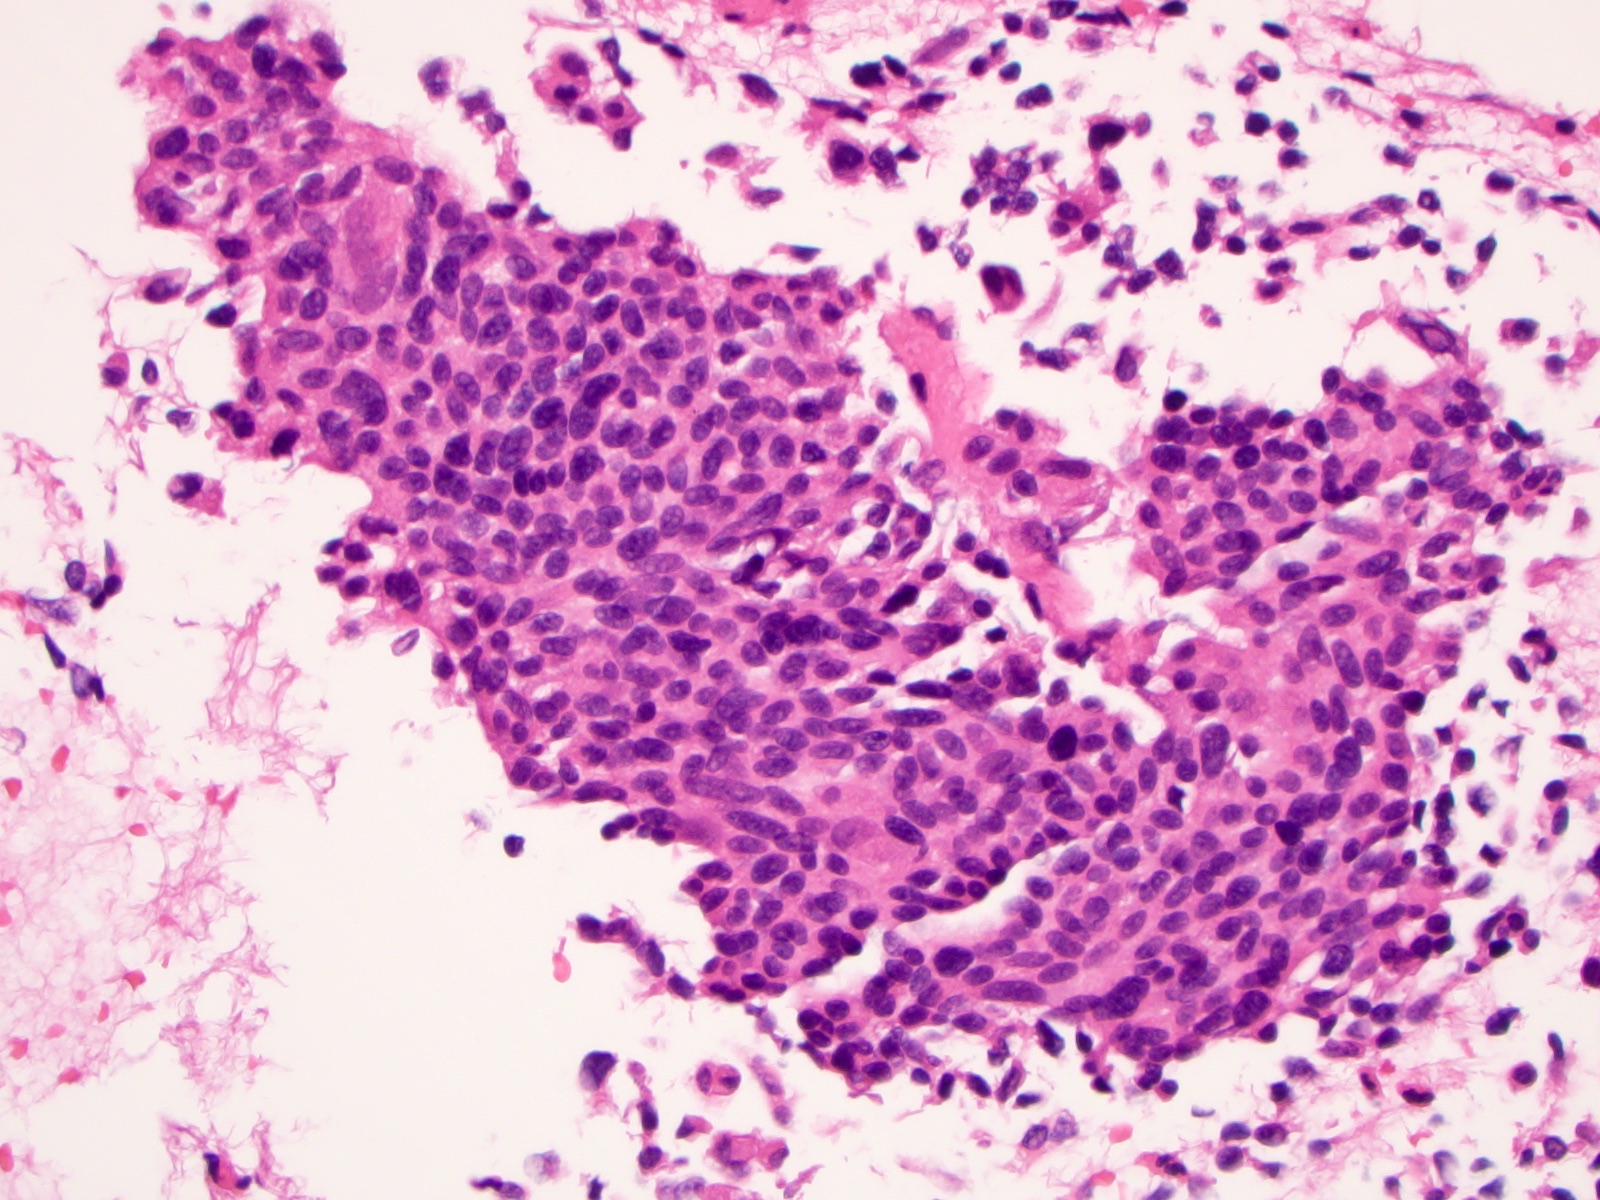

Microscopic (histologic) description

- Wide variety of morphology, can mimic any other thyroid malignancy

- Round, plasmacytoid, polygonal or spindle cells in nests, cords or follicles; often mixtures of these cells

- Round nuclei with finely stippled to coarsely clumped chromatin and indistinct nucleoli, occasional nuclear pseudoinclusion

- Eosinophilic to amphophilic granular cytoplasm due to secretory granules

- Generally low mitotic figures

- Stroma has amyloid deposits from calcitonin, prominent vascularity with glomeruloid configuration or long cords of vessels (Am J Surg Pathol 1995;19:642), coarse calcifications, occasional psammoma-like bodies

- Mucin in 42% (Arch Pathol Lab Med 1983;107:70)

- Often angiolymphatic invasion

- Occasionally marked neutrophilic infiltrate, oncocytic tumor cells, papillary patterns

- May entrap follicles

- C cell hyperplasia present in familial but not sporadic cases

Microscopic (histologic) images

Contributed by Shuanzeng Wei, M.D., Ph.D., Joseph Christopher Castillo, M.D. and Mark R. Wick, M.D.

AFIP images

Images hosted on other servers: